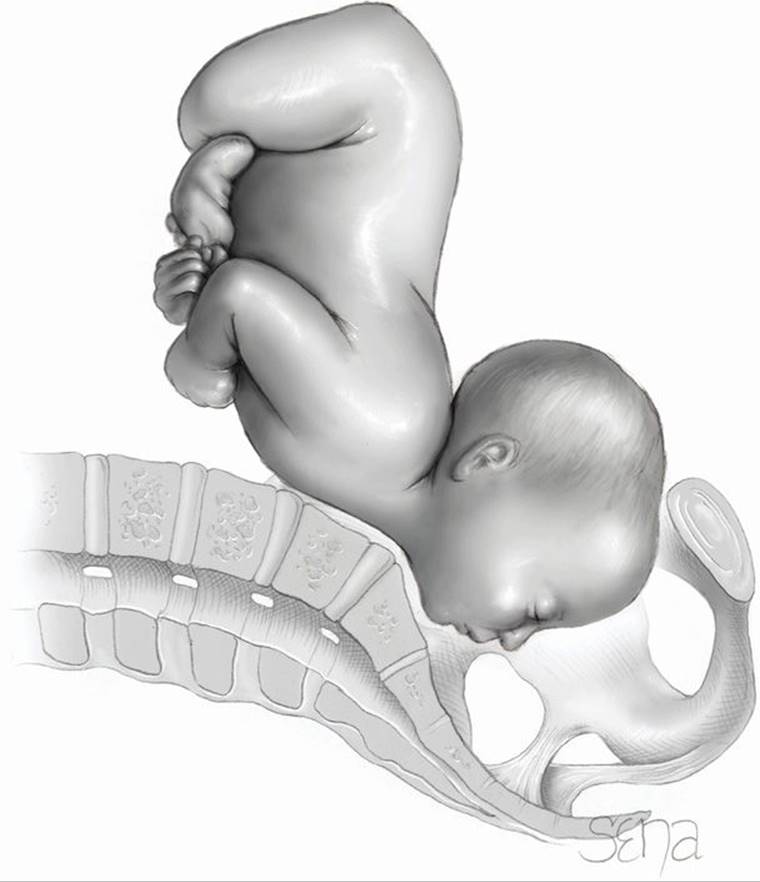

Dystocia as described by Williams (1903) in the first edition of this text is still true today. Figure 23-1 demonstrates the mechanical process of labor and potential obstacles. The cervix and lower uterus are shown at the end of pregnancy and at the end of labor. At the end of pregnancy, the fetal head, to traverse the birth canal, must encounter a relatively thick lower uterine segment and undilated cervix. The uterine fundus muscle is less developed and presumably less powerful. Uterine contractions, cervical resistance, and the forward pressure exerted by the leading fetal part are the factors influencing the progress of first-stage labor.

FIGURE 23-1 Diagrams of the birth canal. A. At the end of pregnancy. B. During the second-stage of labor, showing formation of the birth canal. C.R. = contraction ring; Int. = internal; Ext = external. (Adapted from Williams, 1903.)

As also shown in Figure 23-1B, after complete cervical dilatation, the mechanical relationship between the fetal head size and position and the pelvic capacity, namely fetopelvic proportion, becomes clearer as the fetus descends. Because of this, abnormalities in fetopelvic proportions become more apparent once the second stage is reached.